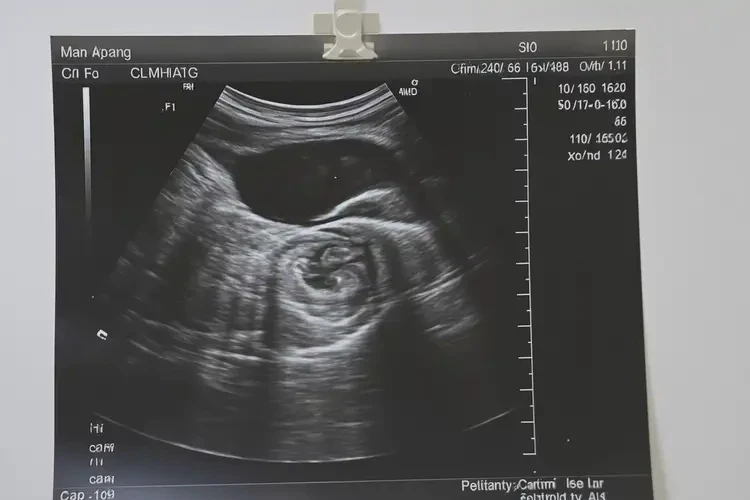

胎心率78次/分钟在孕8周3天的情况下,属于偏低范围,但并不意味着宝宝不能要。 胎心率是评估胎儿健康的重要指标之一,正常情况下,胎心率应在110-160次/分钟之间。在孕早期,胎心率可能会受到多种因素的影响而出现波动。以下是对这一问题的详细分析:

胎心率78次/分钟在孕8周3天的情况下虽然偏低,但并不意味着宝宝不能要。应尽快复查胎心率,并根据检查结果采取相应的措施。是否需要终止妊娠应根据具体情况来决定,以确保母婴健康。